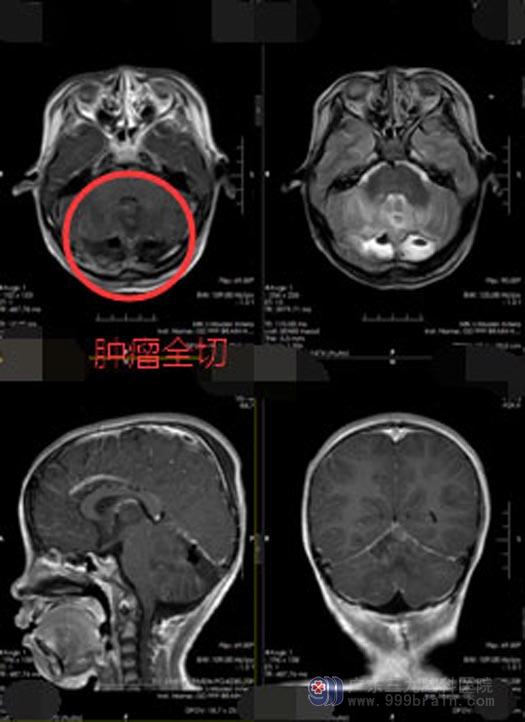

家属同意手术治疗。术中离断错构瘤与下丘脑乳头体之间的联系,术后杨杨康复良好,痴笑性癫痫没有再次发作。中枢性性早熟还需要进一步的内分泌功能治疗。

▲手术后